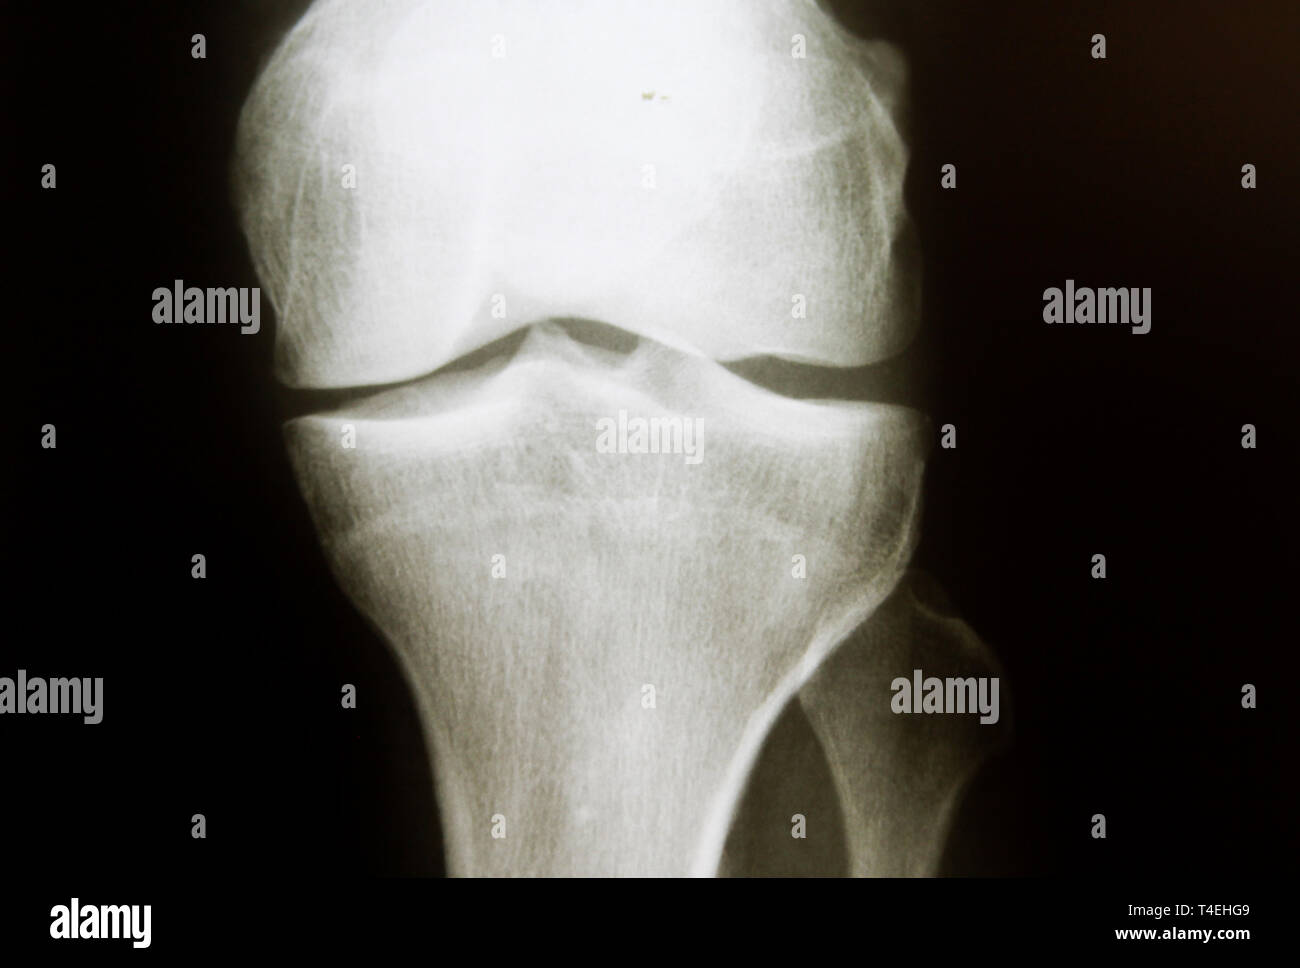

Normal appearances of the knee joint in the growing patient. Citation, doi, disclosures and article data. There mild or borderline patella alta. Education and training, education, plain radiographic studies, paediatric, musculoskeletal joint.

Normal Knee X Ray 13 Year Old - Normal appearances of the knee joint in the growing patient. Web this is a repository of normal pediatric bone xrays and their examples for a quick reference look. It can show broken bones or a dislocated joint. Web normal ap and lateral knee radiographs in an adult male for reference. This article lists examples of normal imaging of the pediatric.

Normal Knee X Ray 13 Year Old - There mild or borderline patella alta. Normal appearances of the knee joint in the growing patient. It can show broken bones or a dislocated joint. Education and training, education, plain radiographic studies, paediatric, musculoskeletal joint. Web database of reference normal pediatric imaging including normal pediatric radiographs, cts, and mris by child age from birth to age 16.